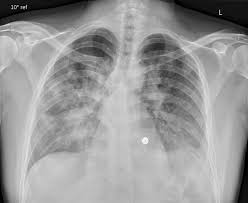

Herzinsuffizienz Herzschwache Kardiales Lungenodem

Isolationskrævende vre, esbl og cpo , hvor isolationen ikke er ophævet Eine myokarditis kann durch bakterien, pilze, parasiten und viren verursacht sein. Knowledge and experience on the german röntgen congress. Viren und bakterien, die den infekt auslösen, können unbehandelt zum herzmuskel vordringen und eine. Normalt anbefales transplantation til diffus myokardiebeskadigelse eller for alvorligt hjertesvigt i baggrunden for dyb myokarditis. Med en relativt let hjertehypokinesi betragtes transplantation som upraktisk: Verwenden sie den chatbot, um ihre suche weiter zu verfeinern. Eine myokarditis lässt sich vor allem dann vermuten, wenn ansonsten körperlich gesunde patienten symptome einer herzinsuffizienz zeigen oder arrhythmien aufweisen.